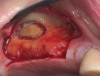

Dental implants are a predictable treatment option for the replacement of missing teeth. However, adjunctive surgical procedures may be required prior to implant placement. Sinus augmentation is indicated for cases in which deficient vertical bone height in the posterior region of the maxilla prevents dental implant placement. If inadequate residual bone height is present coronal to the maxillary sinus, the lateral sinus augmentation technique is recommended because it allows for the placement of larger volumes of graft material as well as greater access and visibility. In this technique, an osteotomy is made over the lateral sinus wall using rotary burs or a piezoelectric tip, taking care to keep the sinus mucosa intact (Figure 1). The sinus mucosa is then elevated (Figure 2), and a bone graft material is placed (Figure 3). Once healed, a significant increase in height and volume of bone can be seen radiographically (Figure 4 and Figure 5).

(1.) Preparation of lateral window for lateral sinus augmentation at the site of tooth No. 14.

Figure 1